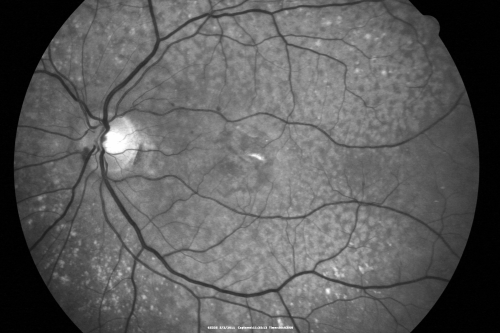

80 year old woman with Reticular Drusen (pseudodrusen) 20/30 Vision

80 year old woman with asteroid hyalosis and macular degeneration.

OPHTHALMIC EXAMINATION: Visual acuity with correction 20/30-3 OD and 20/30-2